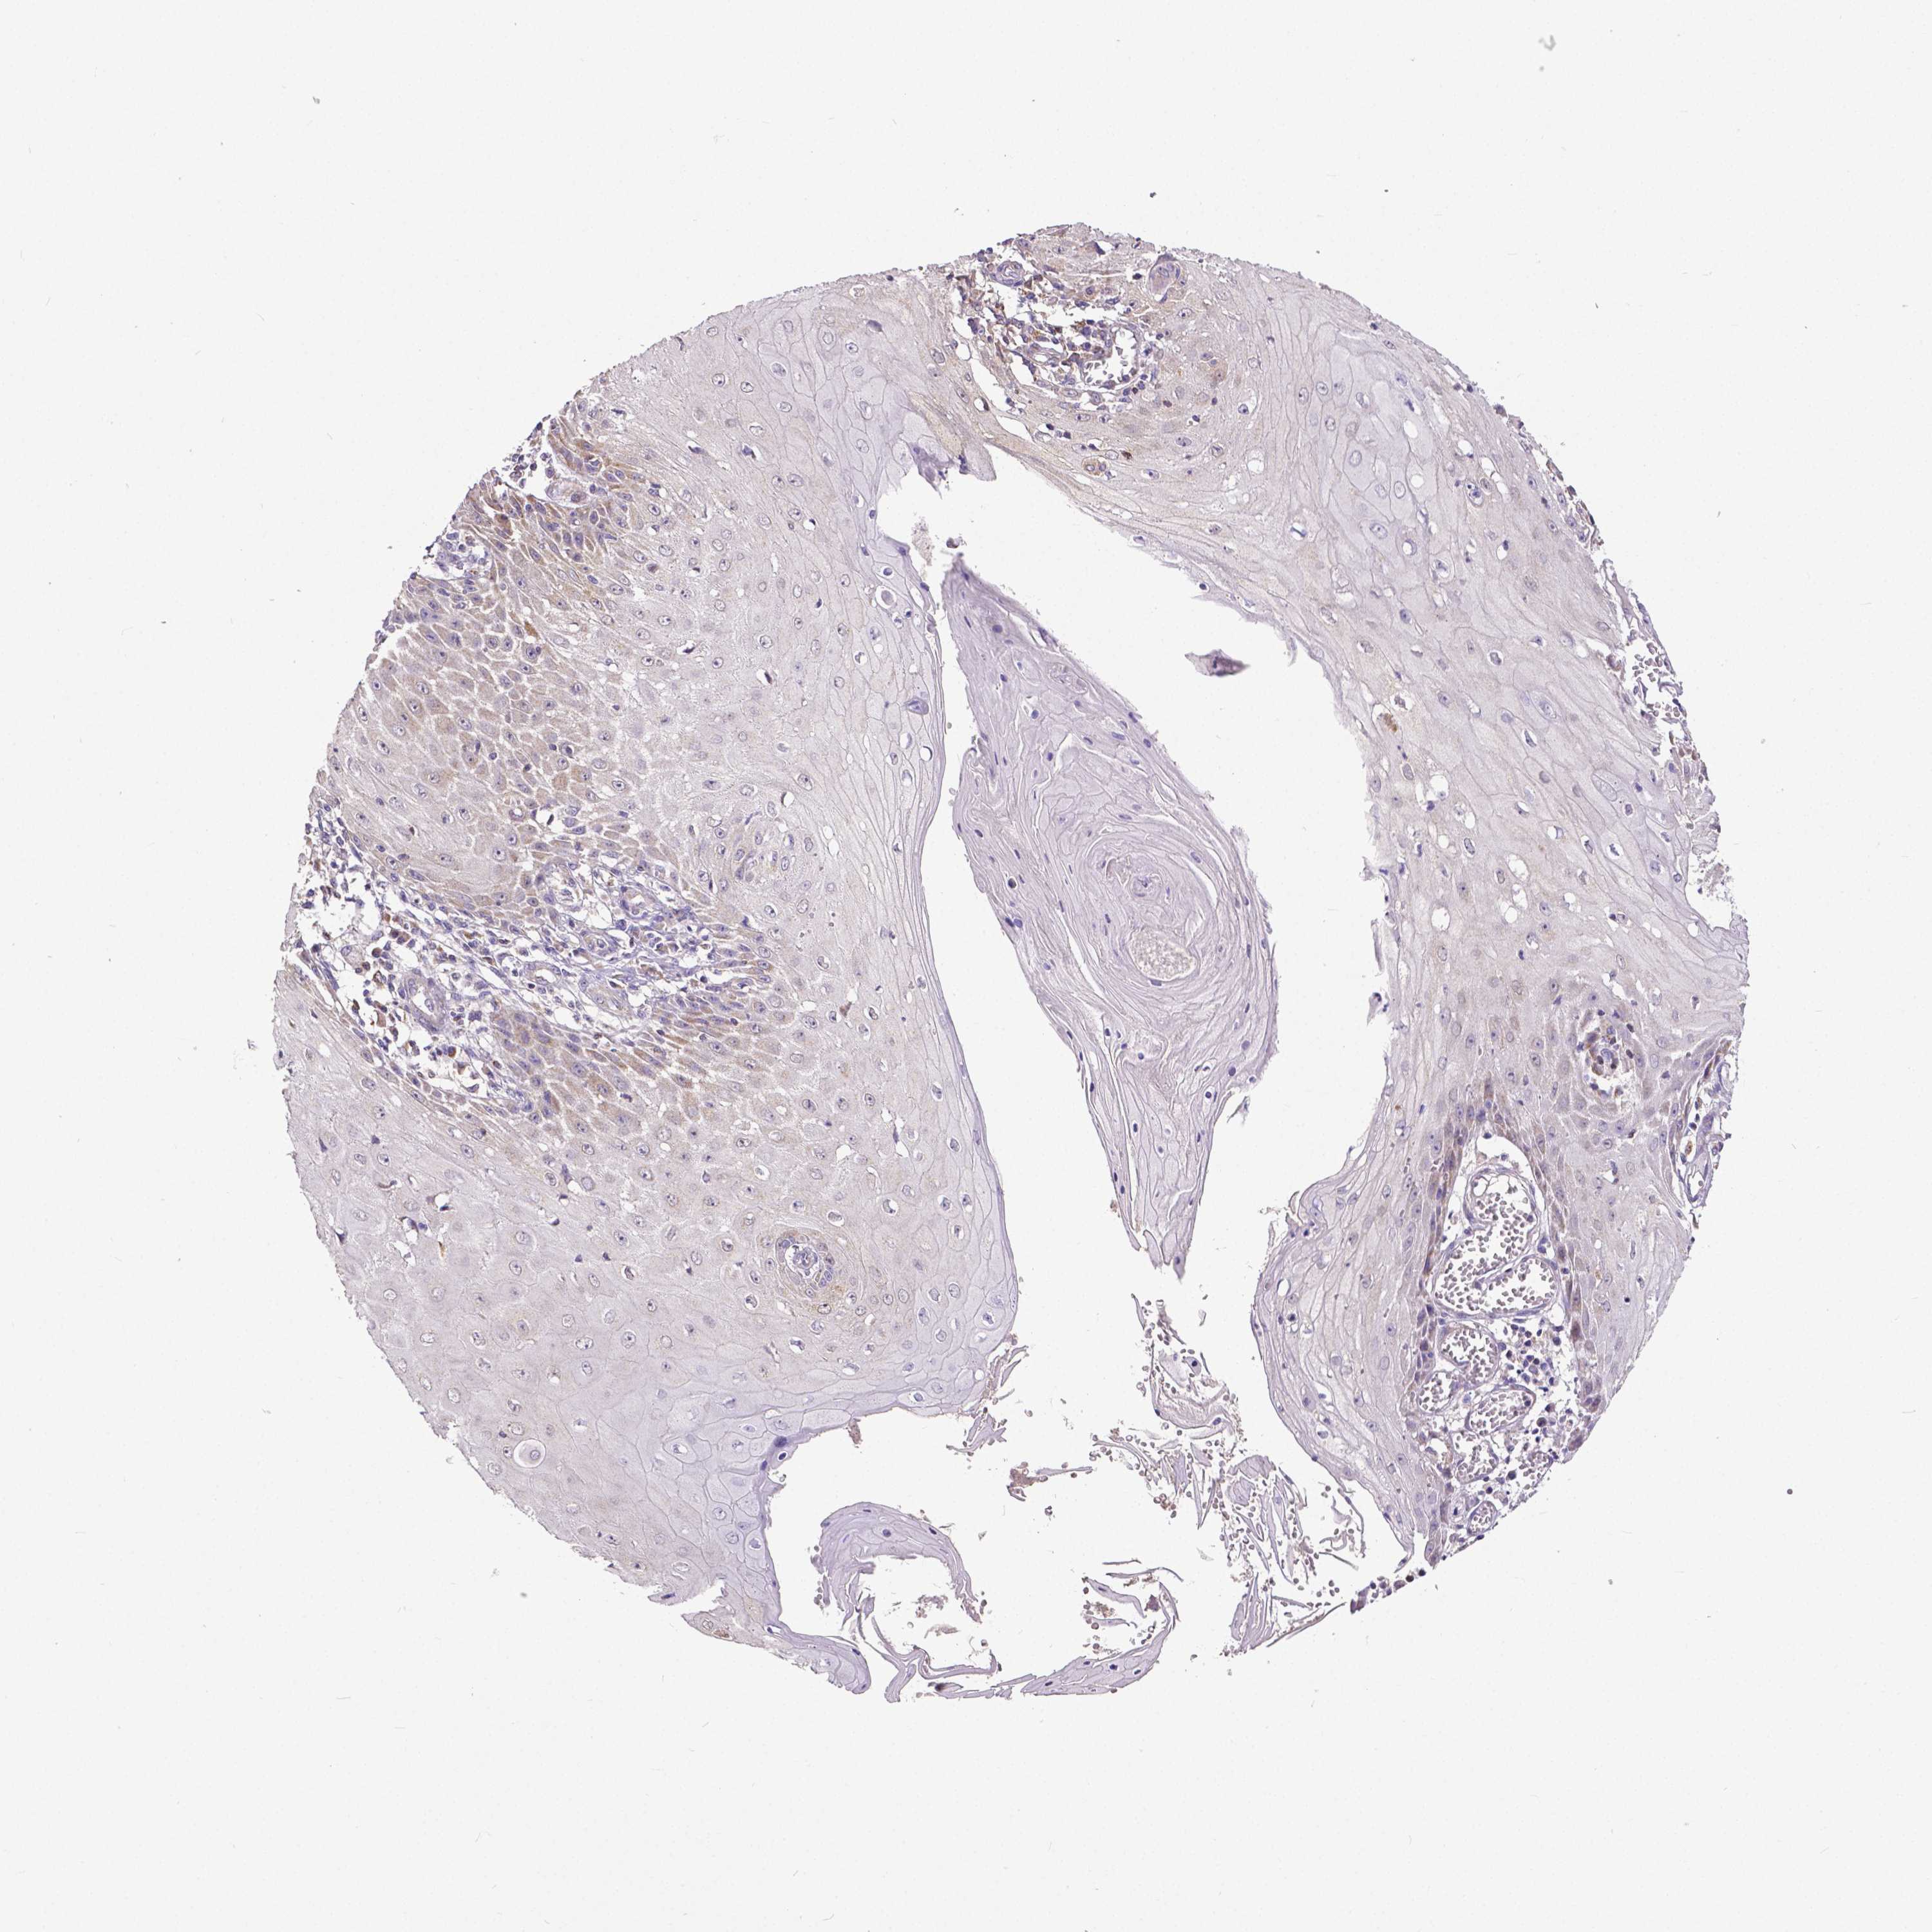

SKIN CANCER - Protein expressioni

A mouse-over function shows sample information and annotation data. Click on an image to view it in a full screen mode. Samples can be filtered based on level of antibody staining by selecting one or several of the following categories: high, medium, low and not detected. The assay and annotation is described here.

Antibody stainingi

Antibody staining in the annotated cell types in the current human tissue is reported as not detected, low, medium, or high, based on conventional immunohistochemistry profiling in selected tissues. This score is based on the combination of the staining intensity and fraction of stained cells.

Each image is clickable and will lead to virtual microscopy that enables deeper exploration of all samples and also displays staining intensity scores, fraction scores and subcellular localization as well as patient and tissue information for each sample.

Antibody HPA008455

Antibody HPA031125

Antibody CAB002781

Antibody CAB068195

Squamous cell carcinoma, NOS

Squamous cell carcinoma, metastatic, NOS

Basal cell carcinoma

Papilloma, NOS